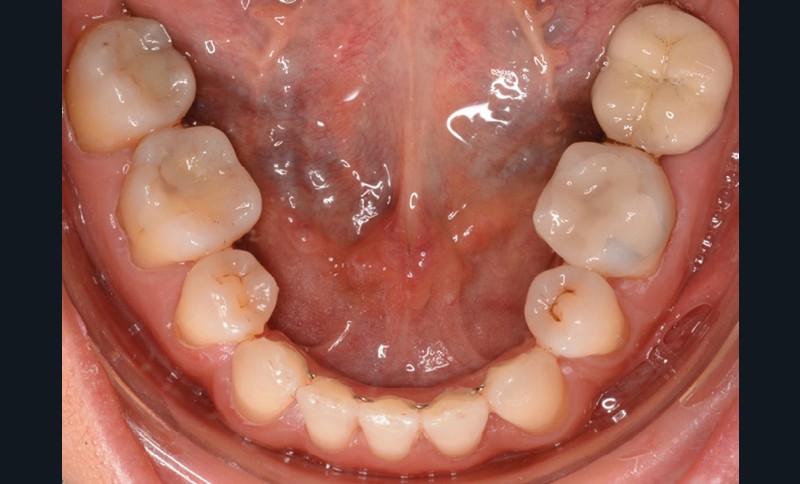

Sur le plan dentaire, la patiente est en classe III droite et gauche, canine et molaire de 6 mm, avec une occlusion inversée antérieure localisée à 11, 12 et 22. Elle présente une dysharmonie dents-arcades sévère, une agénésie d’une incisive mandibulaire est à signaler, et les troisièmes molaires ont été extraites à l’âge de 21 ans.